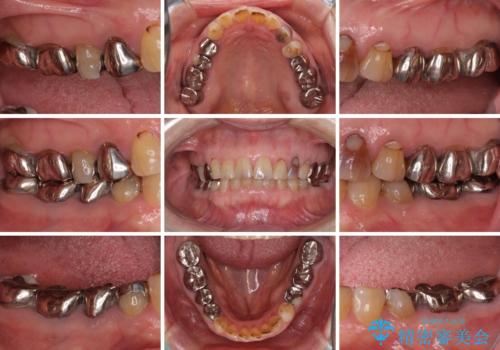

- 奥歯に装着されている銀歯を全て外したいとのことで来院された患者様です。

土台に含まれている金属も含め、奥歯の金属は全て除去し、オールセラミッククラウンやセラミックインレーにて治療することとしました。

- 患者様

- 70代女性

- 1年2ヶ月

- 2-5回

- 治療費の目安: 160万円費用は治療当時の料金となります